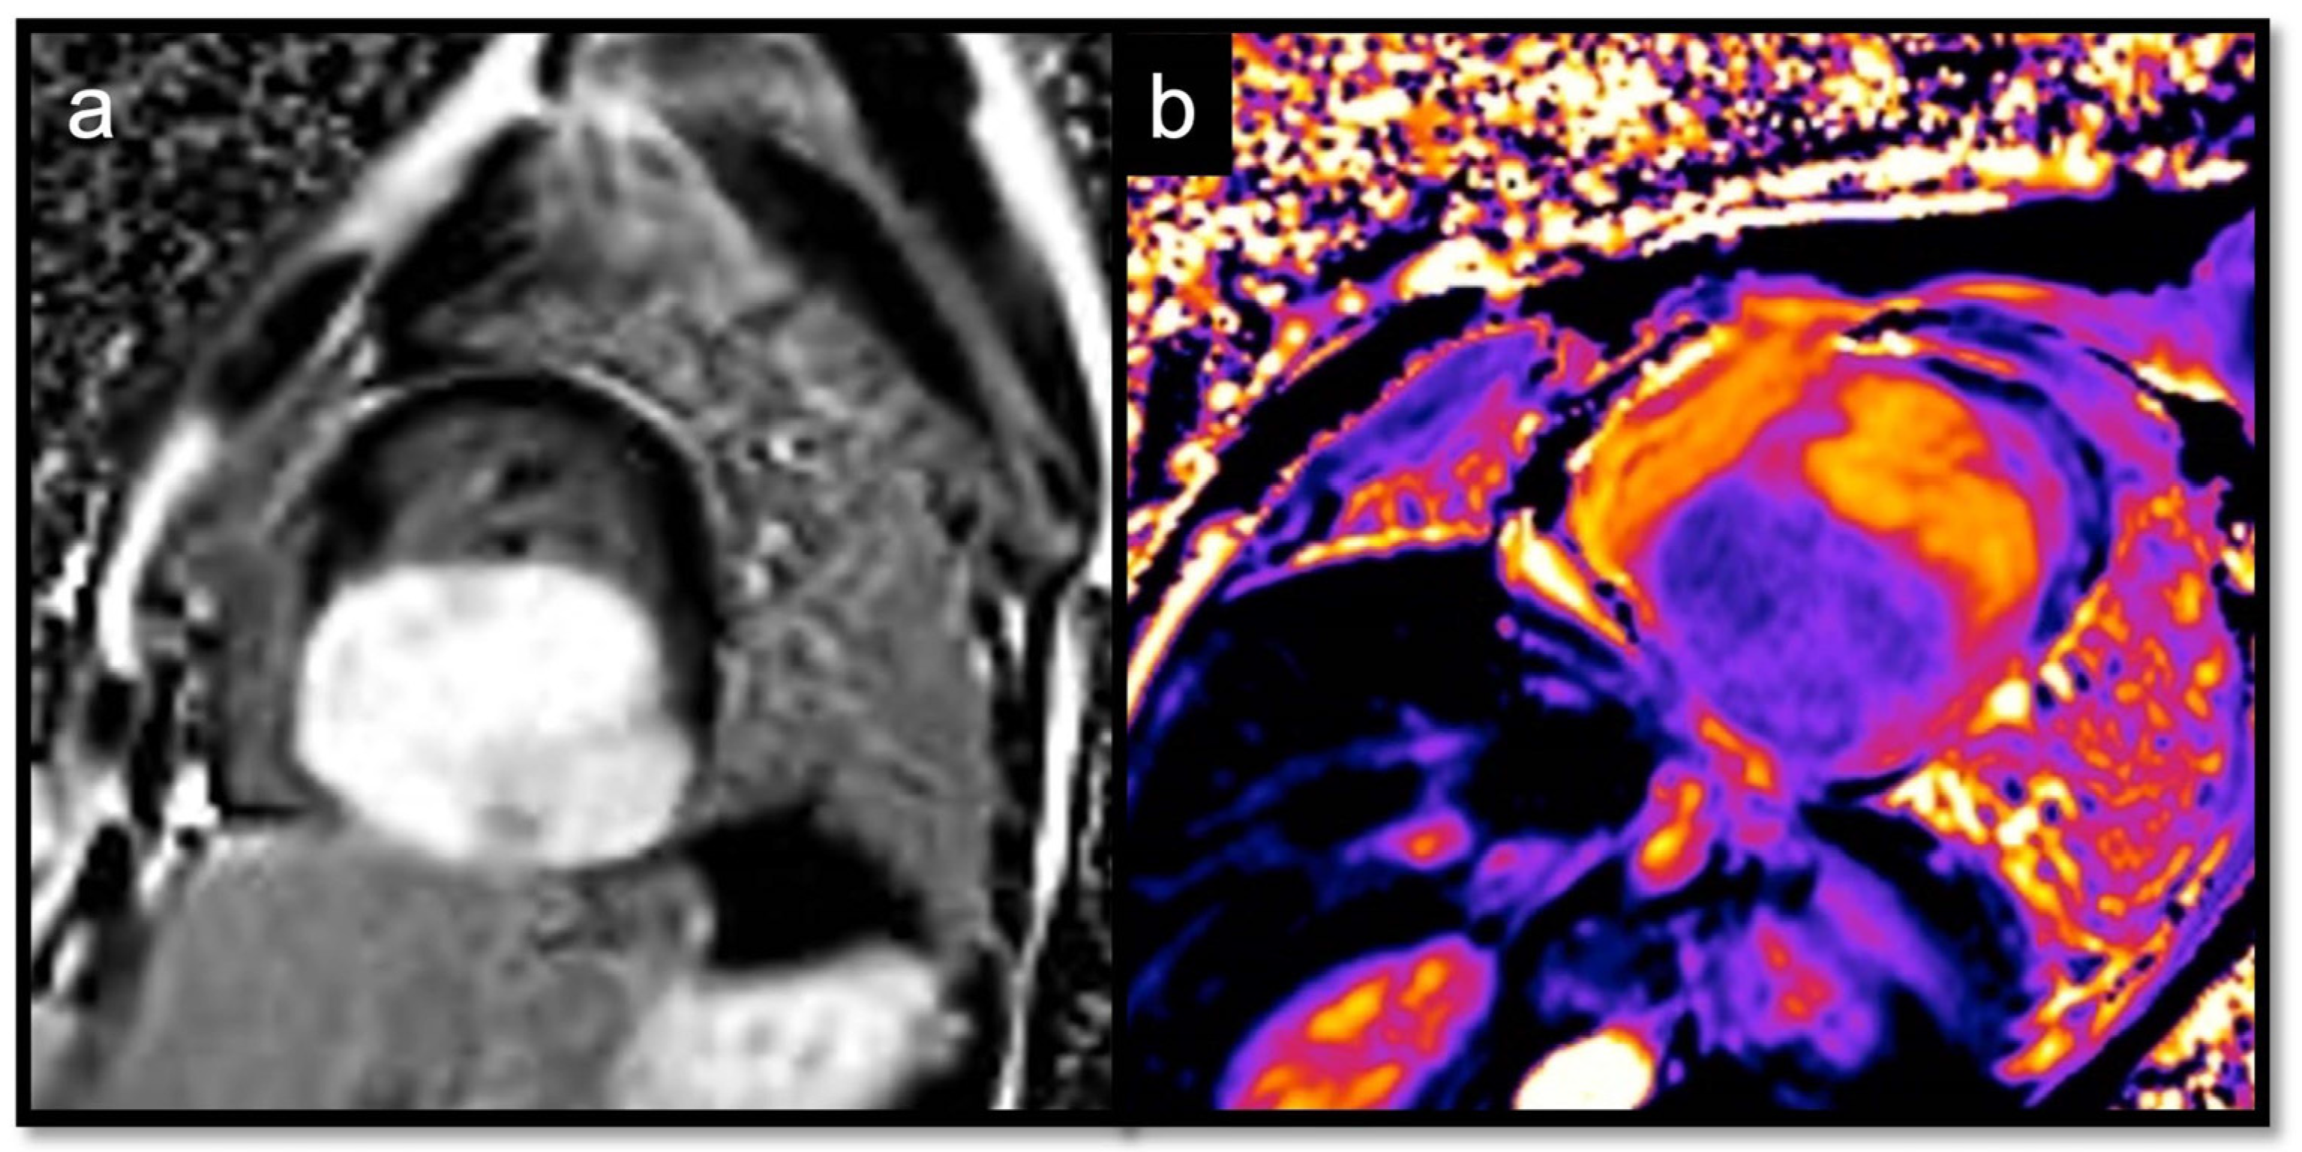

7.2.6. T1 and T2 Mapping

Utility:

Parametric mapping is very useful in patients undergoing evaluation for suspected myocardial disease, and it is also beneficial for the evaluation of cardiac masses. Recent studies evaluating T1 and T2 mapping suggest that parametric mapping increases the ability of CMR to differentiate between cardiac thrombi and masses [58,60,61,62,63]. The analysis of intracardiac tumors and masses with T1 and T2 mapping revealed important differences among the different subtypes, generating multiple T1/T2 profiles according to the etiology [46]:

- Short T1/long T2 for melanoma or lipomas and lipomatosis [64]

- Long T1/long T2 for most tumors, whether benign or malignant, with different degrees in particular for the T1 (close to the myocardium for rhabdomyoma, long or very long for myxomas [65] and fibroelastomas)

Red Flag (!): Heterogenous maps due to hemorrhage or necrosis inside the mass suggest malignancy.

- ECV can be of help in differentiating hypertrophic cardiomyopathy (HCM) from other conditions that may mimic it (Figure 14 and Figure 15) [69].

Figure 14. Suspected HCM in a 14-year-old child, with asymmetric hypertrophy of the left ventricle. In T2w, the septal signal is very different from other myocardial segments (a), and it shows intramyocardial LGE (b), with a slight increase in T1 native values, approximately 1000 ms (normal value < 950 ms in our site) (c) and increased ECV around 41% (normal value < 30%) (d). The diagnosis was overturned and confirmed as a fibroma.